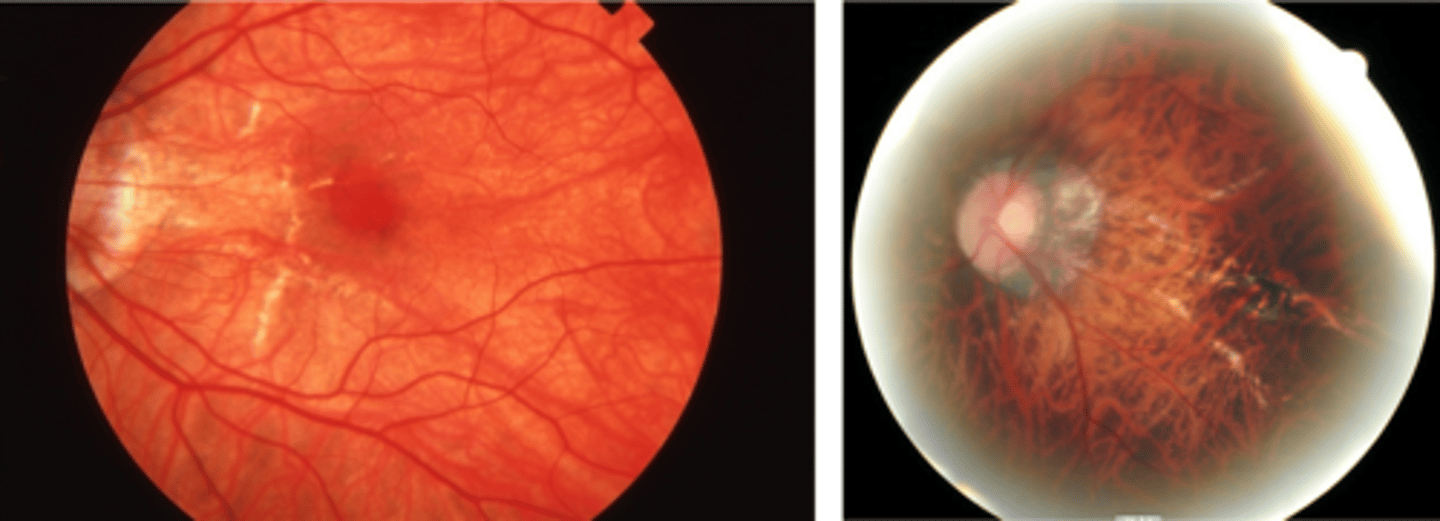

tesselated or tigroid fundus = visibility of choroidal vasculature (A)

What findings of degenerative myopia are seen here?

PPA

crescent

lacquer cracks

What are lacquer cracks and what causes them?

breaks in Bruch's membrane that can expand and contract, mostly seen in degenerative myopia

How do lacquer cracks appear on fundoscopy?

jagged, irregular yellow lines showing sclera in the posterior pole

What is the main complication of lacquer cracks?

CNV in 29% of pt's

What are angioid streaks and what type of atrophy do they lead to?

breaks in Bruch's membrane in a radiating fashion emanating from the ONH = leads to RPE, PR's, choriocapillaris atrophy

What causes angioid streaks?

weakened, calcified Bruch's membrane, often in connective tissue disease = bilateral